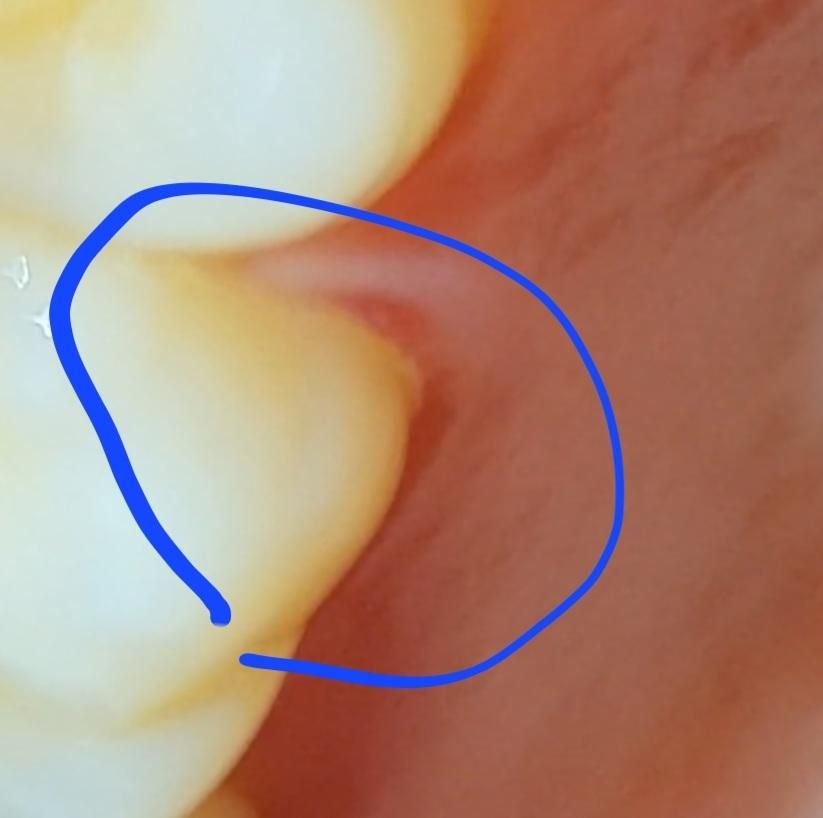

스케일링하고 잇몸 손상 온것 같은데 회복되나요?

알수없는 치통 때문에 어금니 쪽 잇몸 스케일링 세게 했는데 저렇게 패였습니다 회복되는건가요?

아니면 치위생사가 실수하신건가요?

• 1번 째 사진

치석으로 채워져 있던 부위에 치석이 제거가 되면서 파인 것으로 보일수 있으나, 시간이 지나면 좋아지게 되기에 걱정하지 않으셔도 됩니다.

잇몸에 치석이 붙어 잇는경우 치석을 제거하고 나면 저렇게 보이는경우가 잇습니다 .시간이 지나면 괜찮아 지니 너무 걱정하지마세요.

스케일링을 하면 잇몸에 상처가 나거나 할 수 있습니다. 하지만 내 몸의 상처는 대부분 이 주 정도가 지나면 아물기 때문에 해당 부위를 자극하지 않는 것이 좋습니다.

스케일링은 부작용이 없으므로 위생사가 실수를 한다고 해서 잇몸이 파이지는 않습니다. 잇몸이 퇴축되는 건 염증에 의해서 입니다.

스케일링 후 일시적으로 잇몸 부위 통증, 출혈은 있을 수 있고 국소적으로 약했던 잇몸부위가 약간 찢어질 순 있습니다 다만 1~2주면 괜찮아지니 너무 걱정하지 않으셔도 됩니다